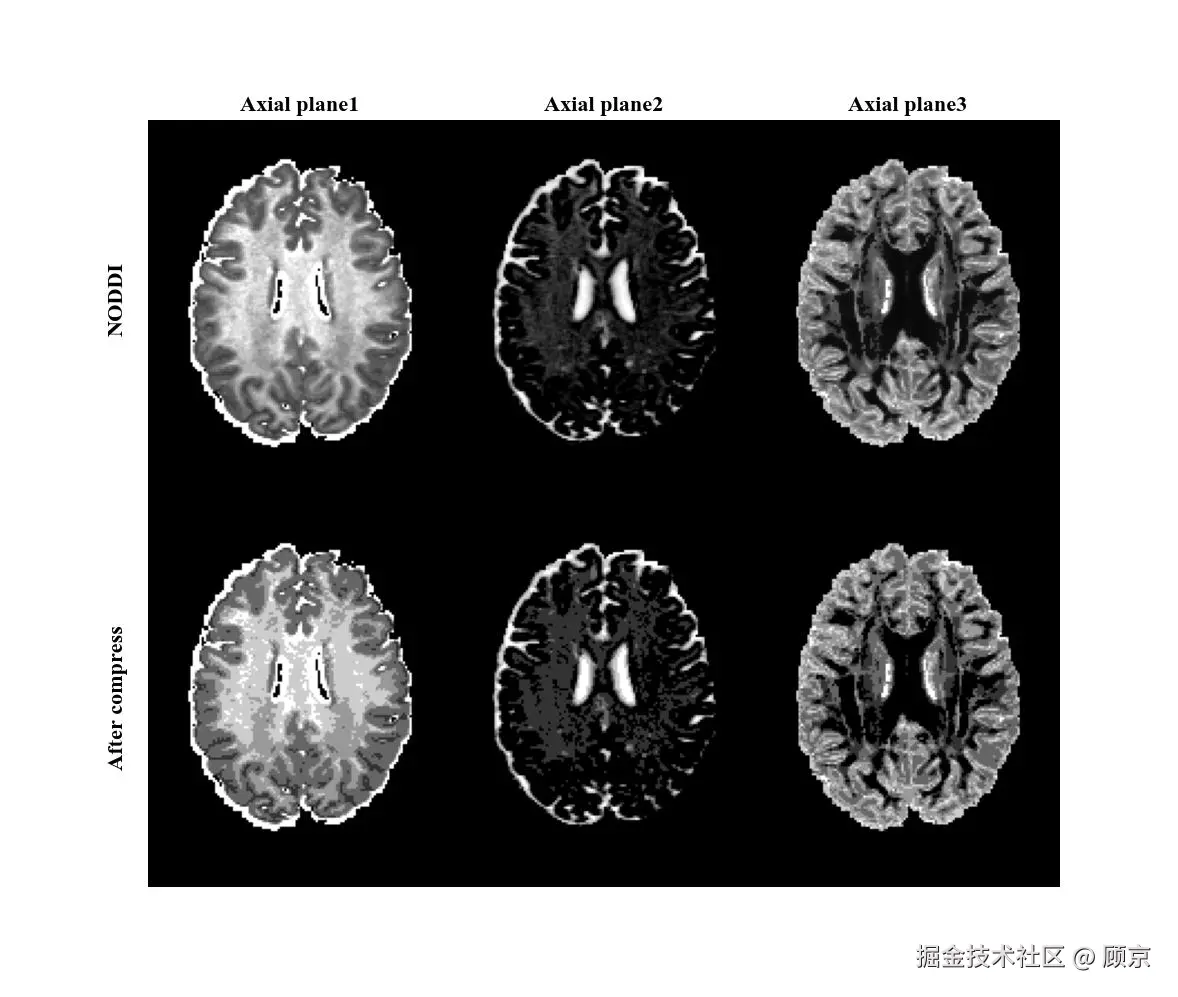

量化

量化可以将连续值变为离散值,应用非常广泛,如图像压缩等。连续值变为离散值,自然就丢失了一些信息,因此它也是图像降级操作,如图7所示。

compress.jpeg

图7 图像量化操作

图像降级操作的实现有很多,下面是通过四舍五入方式实现的。如果quality很大,则量化因子比较小,四舍五入对其影响就比较小,图像几乎没有被量化。如果quality比较小,比如50,则图像先*2,再四舍五入,此时影响就比较大。